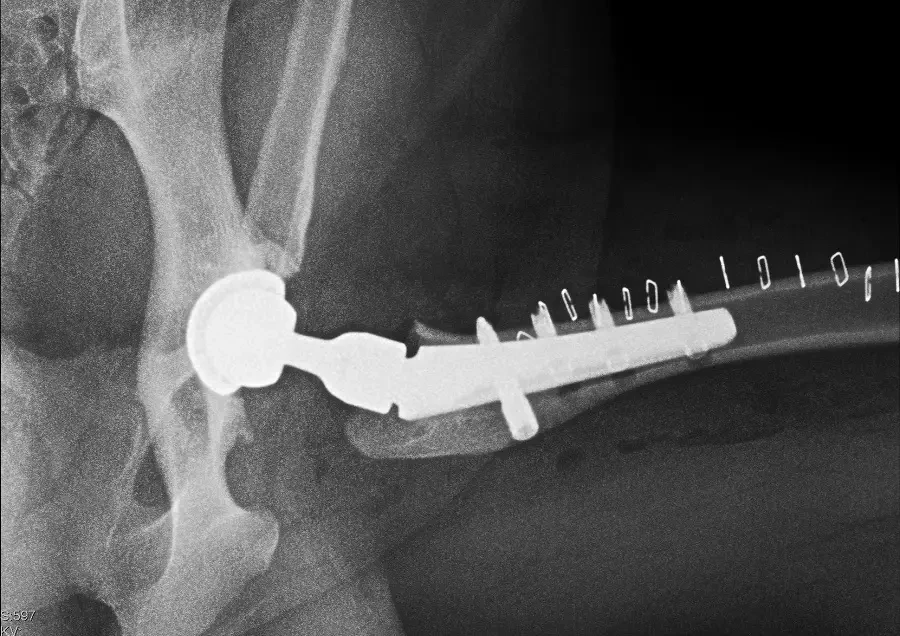

Właściciele pięcioletniego Mailow (border collie) już kilka lat temu zaobserwowali u swojego psa kulawiznę. Postanowili zgłosić się do lekarza weterynarii, który zlecił…